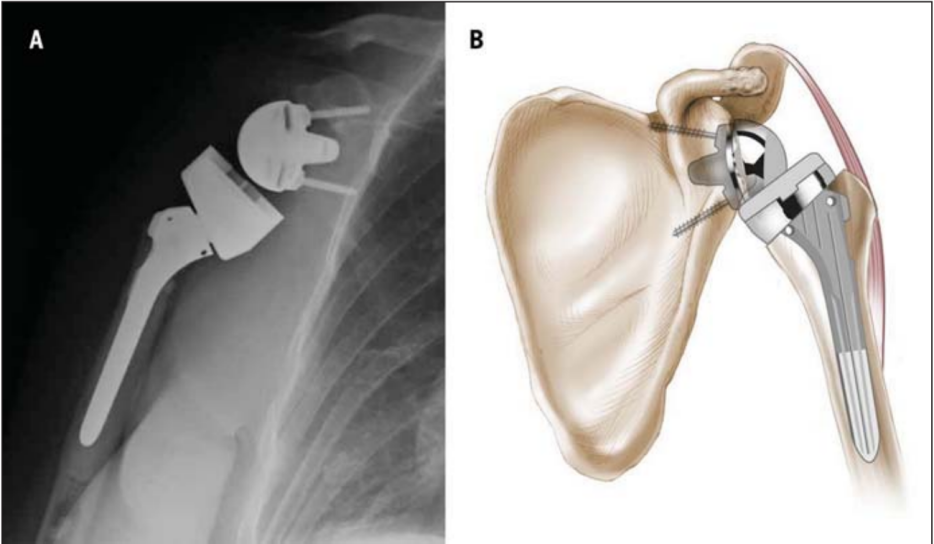

反肩置换术的全称是“反置式人工全肩关节置换术”(RTSA),是指肩关节假体的球形关节面位于肩胛骨关节盂侧,而盂杯位于肱骨近端的半限制性人工全肩关节。

反肩假体设计在生物力学上的优点在于通过旋转中心内移使更多的三角肌纤维参与了肩关节外展和前举运动,通过肱骨侧假体下移使参与肩关节活动的三角肌处于更大的张力状态。这些因素综合作用的目的在于在肩袖缺失情况下能更好地发挥三角肌的功能。

反肩假体构成 反肩人工关节假体的安置